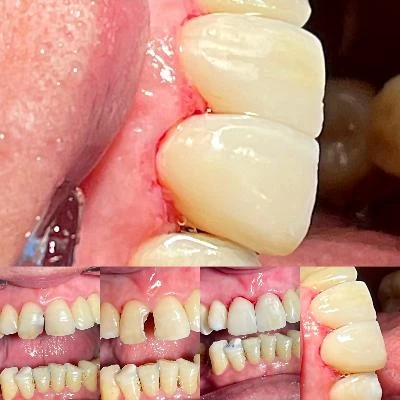

الدكتور فتح اله عباسپور طبيب أسنان

مجال النشاط الدكتور فتح اله عباسپور طبيب أسنان